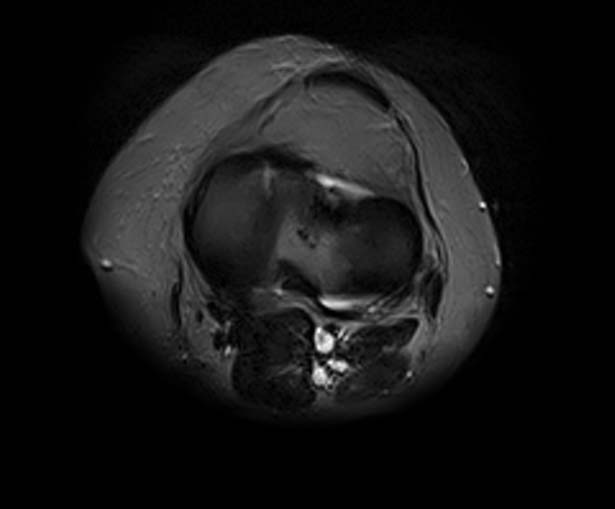

добрый день! Не очень понятен принцип, по которому отбирались снимки МРТ. Большинство из них не показательны. Вижу пока только повреждение хряща на феморопателлярной поверхности. Хлтелось бы посмотреть диск целиком

На снимках повреждений наружного мениска не вижу и кисты мениска не вижу. Есть повреждение хряща на передней поверхности внутреннего мыщелка бедра. Вполне может оказаться, что повреждение лоскутное. А какая консервативная терапия проводилась?